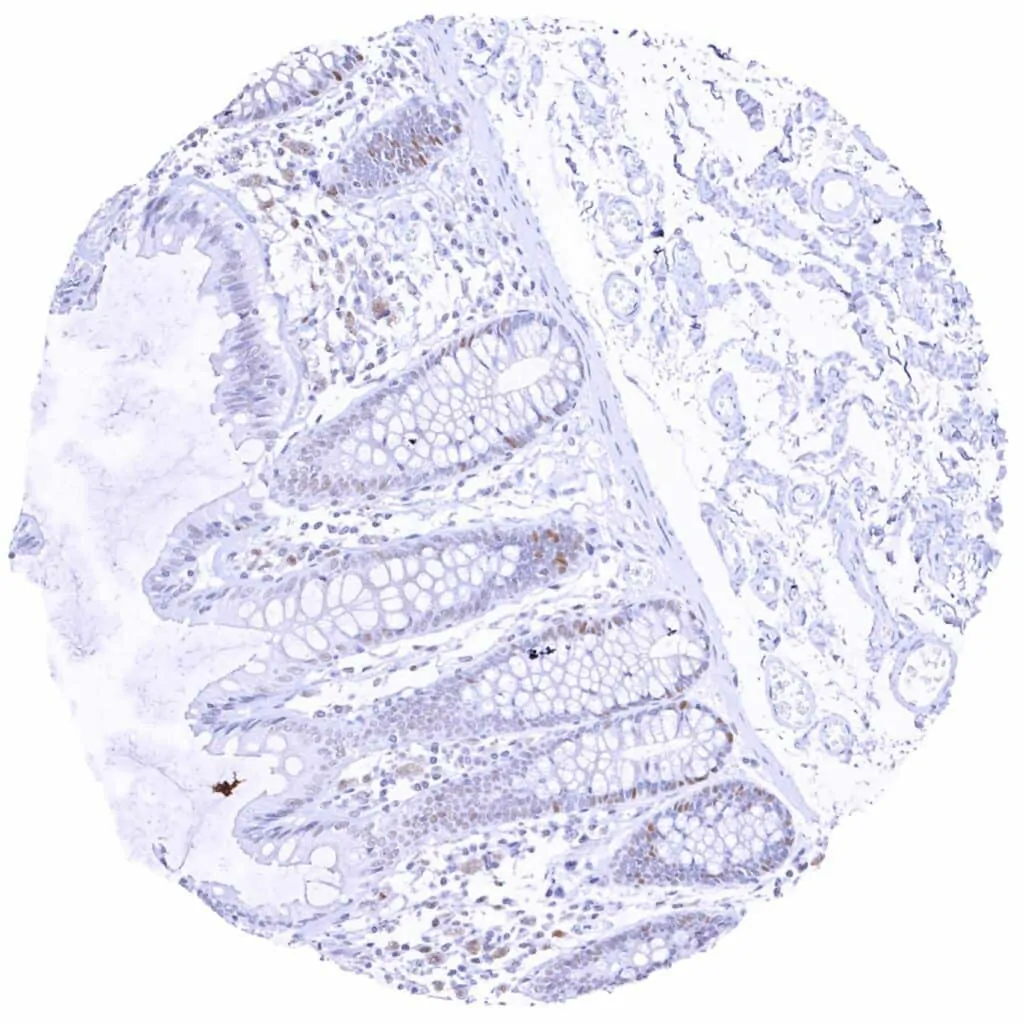

Colon descendens, mucosa – Weak to moderate Cyclin E1 staining of a large subset of crypt cells

Duodenum, mucosa – Weak to moderate Cyclin E1 staining of a subset of crypt cells

Rectum, mucosa – Weak to moderate Cyclin E1 staining of a large subset of crypt cells